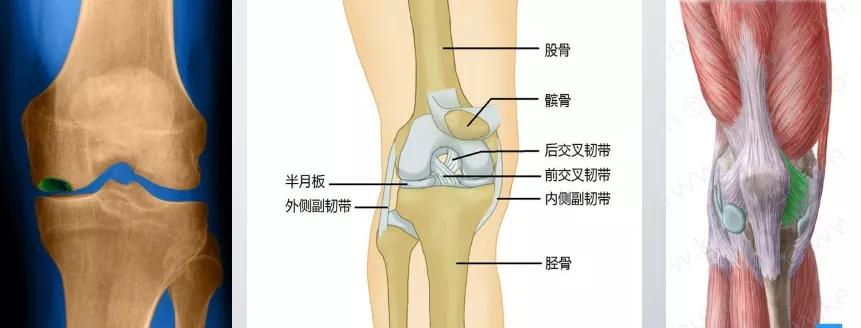

其稳定性全靠关节内外的韧带和肌肉

关节软骨

关节炎早期为关节软骨、半月板的磨损

关节软骨、半月板为骨与骨之间的垫子

半月板的中心部位、关节软骨无血管